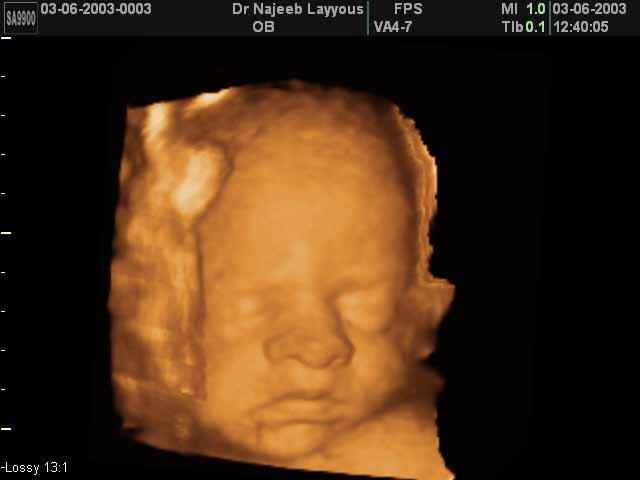

- صور لوجه الجنين في داخل الرحم

صور لوجه الجنين بجهاز الالتراساوند ثلاثي الأبعاد | الدكتور نجيب ليوس